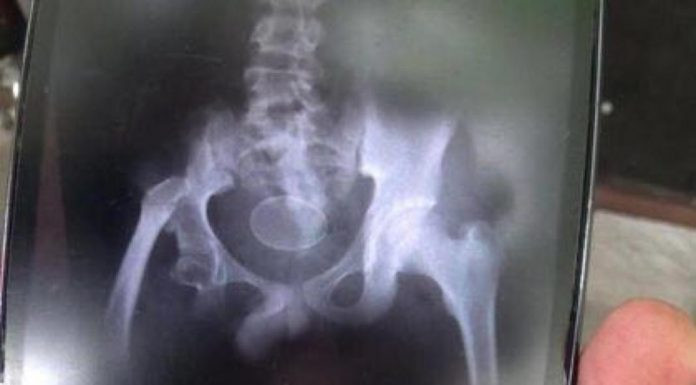

Sau khi chụp X- quang, các bác sĩ đã hết sức bối rối khi nhìn thấy một vật thể có hình dạng và kích thước tương tự như một quả trứng ở vùng chậu của cậu bé.

Phim chụp X- quang hiện lên vật thể lạ giống trứng.